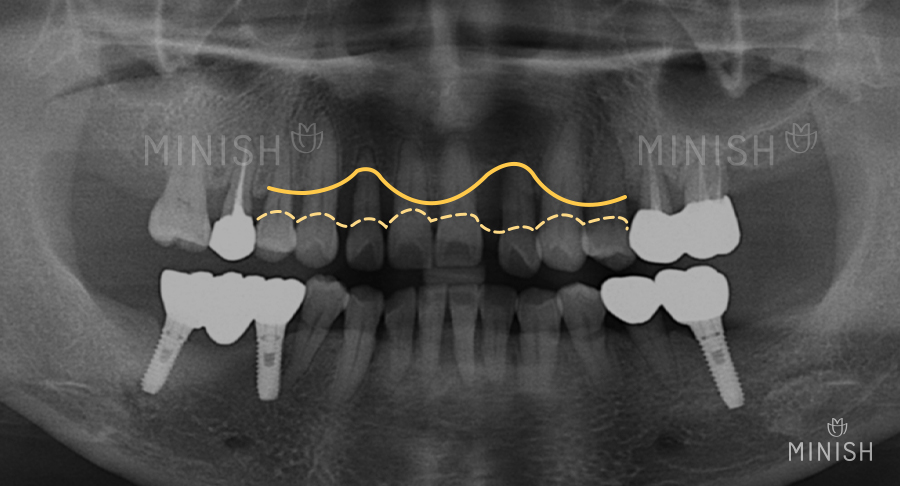

▲ 잇몸 뼈가 심하게 소실된 2개의 작은 앞니는 발치가 필요한 상황입니다.

하지만 잇몸 뼈가 정상 범위에 비해 매우 부족해 임플란트 수술을 시도하기 어렵죠. 인공뼈를 이식하는 등 어렵고 긴 수술 과정에 비해 성공 확률이 희박하기 때문입니다.